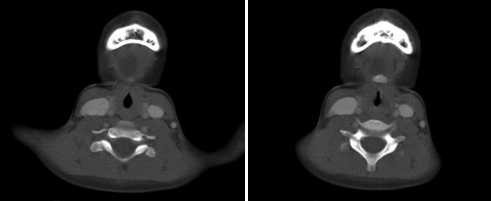

2. 외래로 5세 환아가 내원하였다. 특별한 병력이 없는 환아로, 1개월 전 감기를 앓은 후 턱 가운데 아래가 부었으며, 현재 통증은 없으나 붓기는 호전되지 않아 타원에서 Neck CT 시행 후 아래와 같은 그림 소견으로 내원하였다. 가장 가능한 ‘선천성 경부 종물’ 진단은 무엇인가?

① 갑상설관 낭종

② 새결 기형낭종

③ 하마종

④ 갑상선 낭종

⑤ 악하선 종양